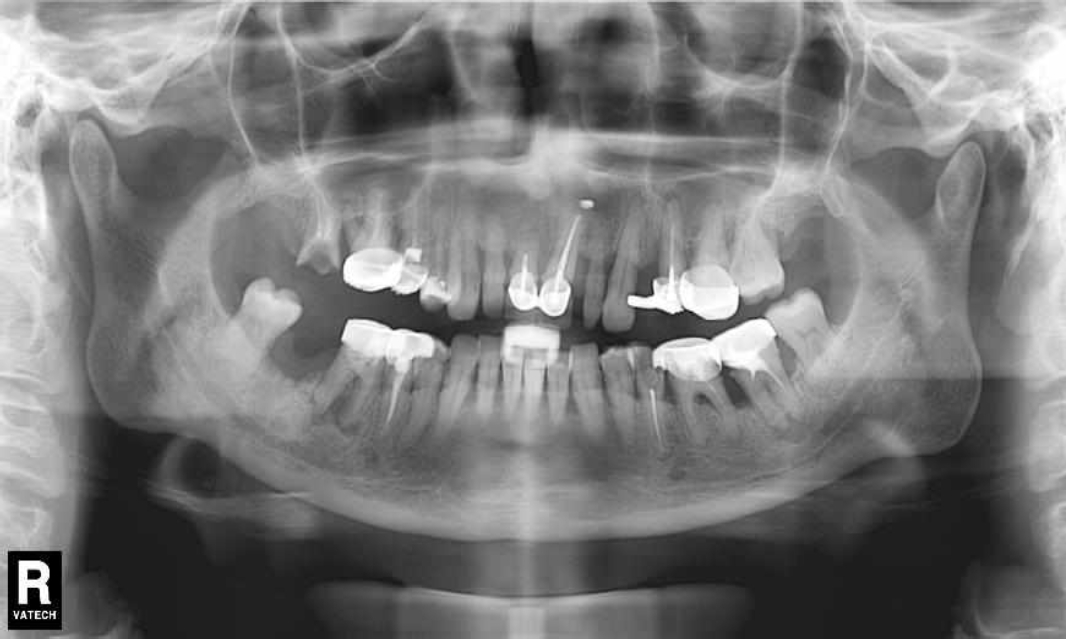

После проведения осмотра пациента приступаем к рентгенологическому исследованию, которое является дополнительным методом в диагностике заболеваний пародонта, но необходимо для постановки окончательного диагноза. Для этой цели используют полную серию прицельных рентгенограмм или КЛКТ.

Ранее у пародонтолога не наблюдалась. При осмотре выявлены: неудовлетворительная индивидуальная гигиена полости рта, пародонтальные карманы до 7 мм, обильная кровоточивость и гноетечение из пародонтальных карманов, подвижность зубов 4.2, 4.1, 3.1, 3.2 II степени, обильные над- и поддесневые зубные отложения (рис. 1). На ортопантомограме отмечается резорбция костной ткани до ½ длины корня, очаги остеопороза (рис. 2). Пациенту был поставлен диагноз хронический генерализованный пародонтит тяжелой степени тяжести. При осмотре была составлена пародонтограмма с использованием компьютерного зондирования (рис. 3).

Рис. 2. Ортопантомограмма исходной ситуации пациента состояния полости рта